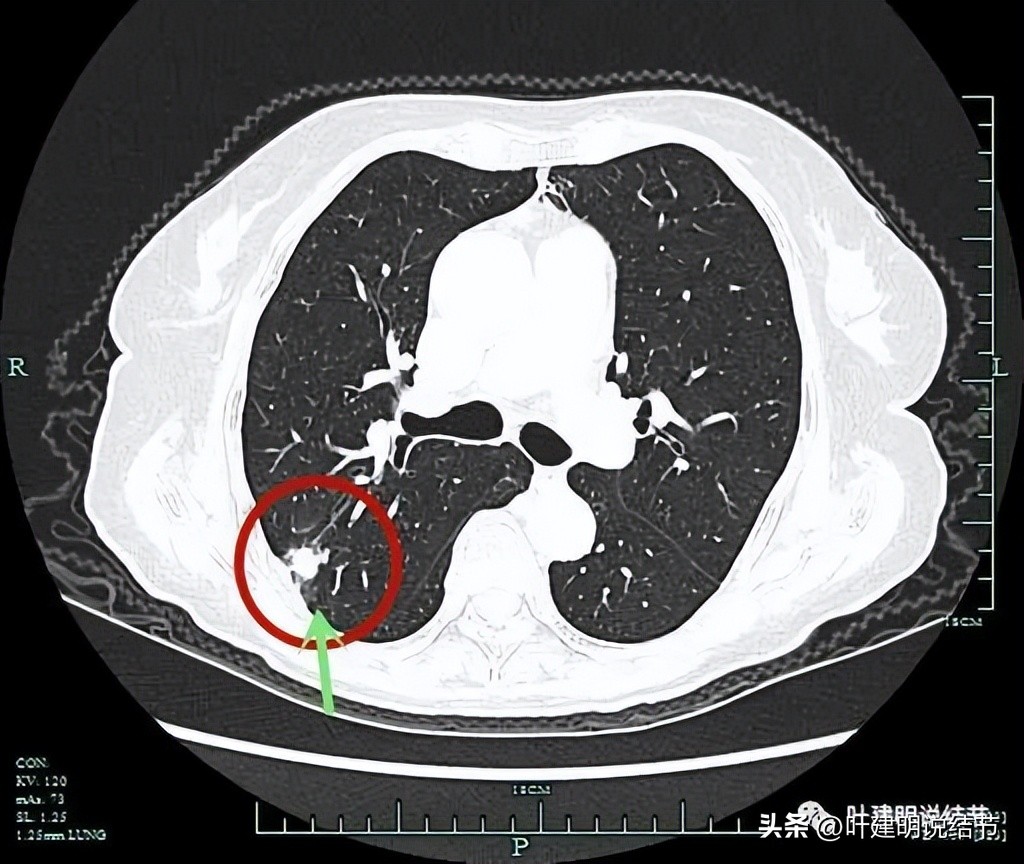

病灶边缘区域有磨玻璃成分,但磨玻璃成分的边界显得有些模糊(绿色箭头)。